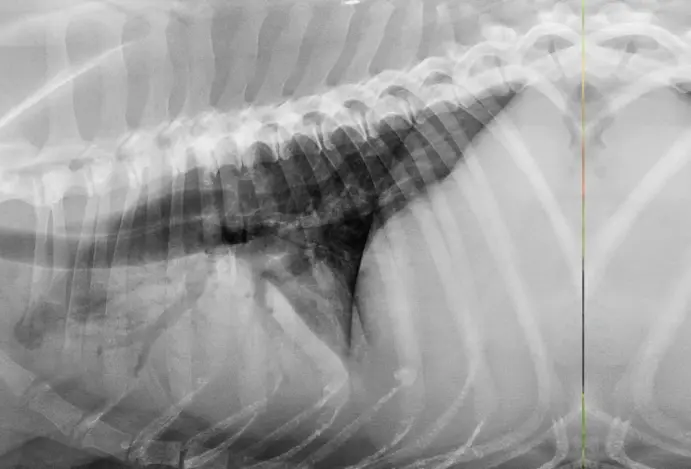

Para chegar ao diagnóstico, o veterinário faz a anamnese do animal com ajuda do tutor, exame físico completo para detectar possíveis sinais clínicos e identificar doenças secundárias. O especialista pode ainda solicitar exames complementares como hemograma completo, radiografia e ultrassonografia torácicas, ecocardiografia e mensuração de proteínas séricas. Este último permite avaliar o estado nutricional e detectar doenças renais, hepáticas e hematológicas.